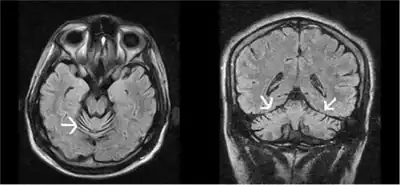

| MRI progressive ataxia due to alpha-tocopherol deficiency | |